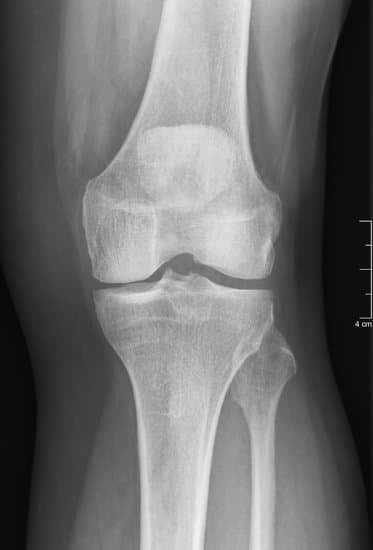

무릎 연골 이식술은 손상된 연골을 복구하기 위해 건강한 연골 조직을 이식하는 수술입니다.

주로 관절염이나 외상으로 인해 연골이 심하게 손상된 경우 시행됩니다.

관절경을 사용해 무릎 내부를 확인한 후 손상 부위를 평가합니다.